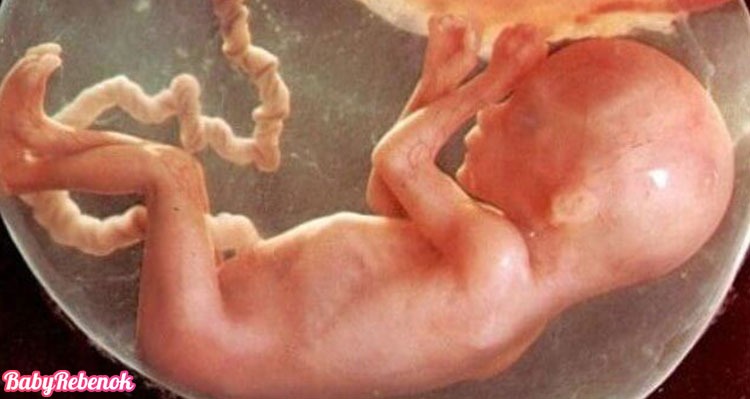

25 недель беременности: Как выглядит будущий малыш

Раздел: Образы вокруг